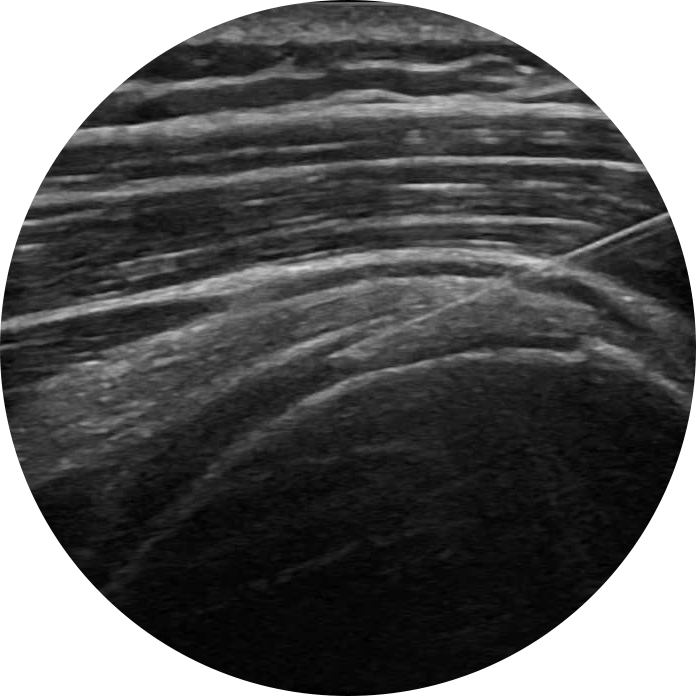

Visita ecoguidata

🔎 La visita ecoguidata di spalla è una valutazione clinica corredata da una contestuale ecografia dinamica e comparativa che permette di “guardare” dentro la struttura della spalla e identificare subito le cause del dolore.

Infiltrazioni ecoguidate

L’ecografo consente di eseguire le infiltrazioni alla spalla con estrema precisione permettendo il continuo monitoraggio del percorso dell’ago fino al tessuto bersaglio garantendo la massima efficacia terapeutica.